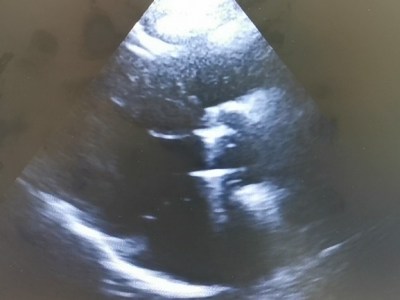

Trombul intracardiac

Tromb (cheag) cardiac, apărut prin perturbarea circulației intracardiace a sângelui, în acest caz prin contracție deficitara a muschiului cardiac cu scăderea forței de…